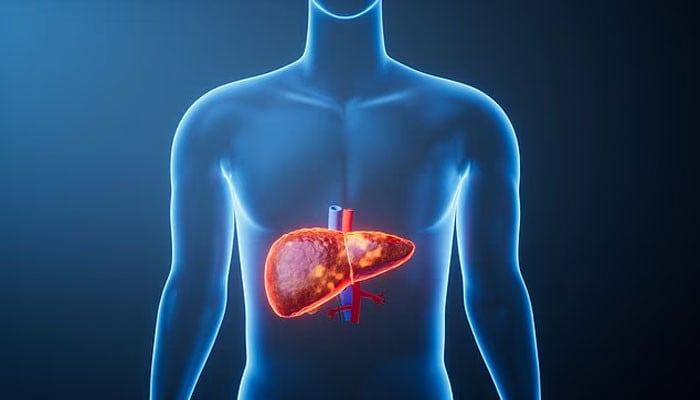

ایک بڑی تحقیق میں خبردار کیا گیا ہے کہ دنیا بھر میں لاکھوں لوگ مہلک جگر کی بیماری کے خطرے سے دوچار ہیں، تاہم ماہرین کا کہنا ہے کہ صرف طرز زندگی میں تبدیلی سے ان کیسز کو نصف کیا جاسکتا ہے۔

ماہرین کے مطابق پوری دنیا میں جگر کی بیماری ایک خاموش وبا کی شکل اختیار کرتی جا رہی ہے اور ہر سال لاکھوں افراد کی جان لے رہی ہے، حالانکہ زیادہ تر کیسز قابل بچاؤ ہیں۔

یہ تحقیق لانسیٹ کمیشن برائے برائے جگر کی صحت نے تیار کی اور اس کے مطابق شراب نوشی، غیر صحت بخش غذا، موٹاپا اور وائرل ہیپاٹائٹس جگر سے متعلق اموات میں اضافے کی بنیادی وجوہات ہیں۔

کمیشن نے دعویٰ کیا ہے کہ طرز زندگی میں تبدیلیوں سے دنیا بھر میں جگر کی بیماری کے بوجھ کو تقریباً نصف تک کم کیا جاسکتا ہے۔ اس کے ساتھ ساتھ الکوحلک مشروبات کی روک تھام، بہتر اسکریننگ اور جلد تشخیص جیسی پالیسیاں بھی مددگار ثابت ہو سکتی ہیں۔

یہ رپورٹ اس وقت سامنے آئی ہے جب برطانوی ماہرینِ صحت خبردار کر رہے ہیں کہ جگر کی بیماری ایک بڑھتا ہوا عوامی صحت کا مسئلہ بنتی جا رہی ہے۔

ادھر دوسری جانب برٹش لیور ٹرسٹ کے مطابق ہر سال 11,000 سے زائد افراد جگر کی بیماری کے باعث ہلاک ہوتے ہیں، جو روزانہ 31 سے زیادہ اموات کے برابر ہے۔

اگرچہ برطانیہ میں کبھی جگر کی بیماری کو زیادہ تر شراب نوشی سے جوڑا جاتا تھا، مگر اب اسے جدید طرزِ زندگی کے عوامل جیسے غیر متوازن غذا، جسمانی سرگرمی کی کمی اور میٹابولک بیماریوں سے بھی منسلک کیا جا رہا ہے۔

میٹابولک ڈس فنکشن سے وابستہ اسٹیٹوٹک جگر کی بیماری جسے پہلے نان الکحل فیٹی لیور بیماری کہا جاتا تھا، موٹاپے، ٹائپ 2 ذیابیطس اور ہائی بلڈ پریشر کی وجہ سے ہوتی ہے۔

یہ اکثر کئی سالوں تک خاموشی سے نشوونما پاتی ہے اور اس کی کوئی واضح علامات ظاہر نہیں ہوتیں، جس کی وجہ سے بہت سے لوگوں کو اس وقت تک اس بیماری کا علم نہیں ہوتا جب تک جگر کو خاصہ نقصان نہ پہنچ چکا ہو۔

کمیشن کے مطابق ڈیجیٹل اشتہارات اور سوشل میڈیا پر بچوں اور نوجوانوں کو نشہ آور اور غیر صحت بخش خوراک کی تشہیر زیادہ دکھا رہے ہیں، جس سے ایسے رویے فروغ پاتے ہیں جو جگر کی بیماری سے جڑے ہوئے ہیں۔